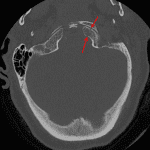

- Nondisplaced left occipital condyle fracture

- Nondisplaced left occipital condyle fracture

Acute nondisplaced left occipital condyle fracture. No traumatic malalignment.

- Occipital condyle fractures are often missed, in part because they are often nondisplaced or minimally displaced. Make sure to look closely at the condyles on all three planes (you can do this at the same time you check alignment at the craniocervical junction)

- Remember that the alar ligaments attach to the occipital condyle. Displaced avulsion fractures are considered unstable injuries concerning for underlying ligament injury, and while you do not need to know the surgical classification schemes, make sure to mention whether or not these fractures are displaced